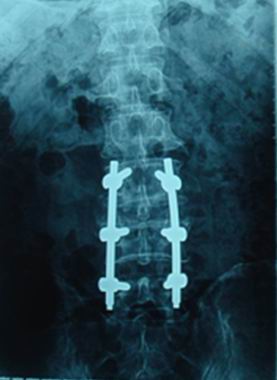

耀彩网自2005年起与威高骨科材料有限公司合作,先后开展了植入器械的研发和产品注册证的申报工作。2006年,耀彩网建立了Ti2448合金材料的企业标准,威高骨科采用Ti2448合金加工了弹性接骨板和脊柱固定系统,并分别报送国家食品药品监督管理局天津医疗器械监督检验中心检验,2008年成功通过了生物学安全性考核。2008年和2009年,Ti2448合金接骨板和脊柱固定系统分别在山东大学附属齐鲁医院、山东省中医院以及中国医科大学附属第一临床医院、吉林大学附属第二临床医院开展了临床试验。目前,两类产品的临床试验已经成功完成,威高骨科材料有限公司已经向国家食品药品监督管理局申报产品注册证。